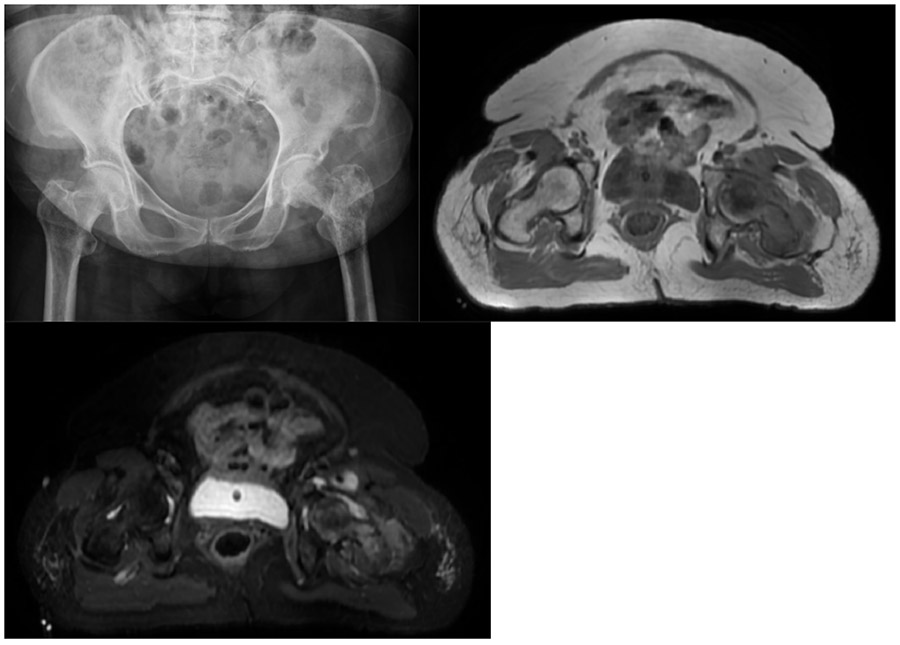

Before the surgery: X-ray shows lytic lesions in the left proximal femur, and MRI also shows a soft tissue component of the tumor that has extended beyond the bone.